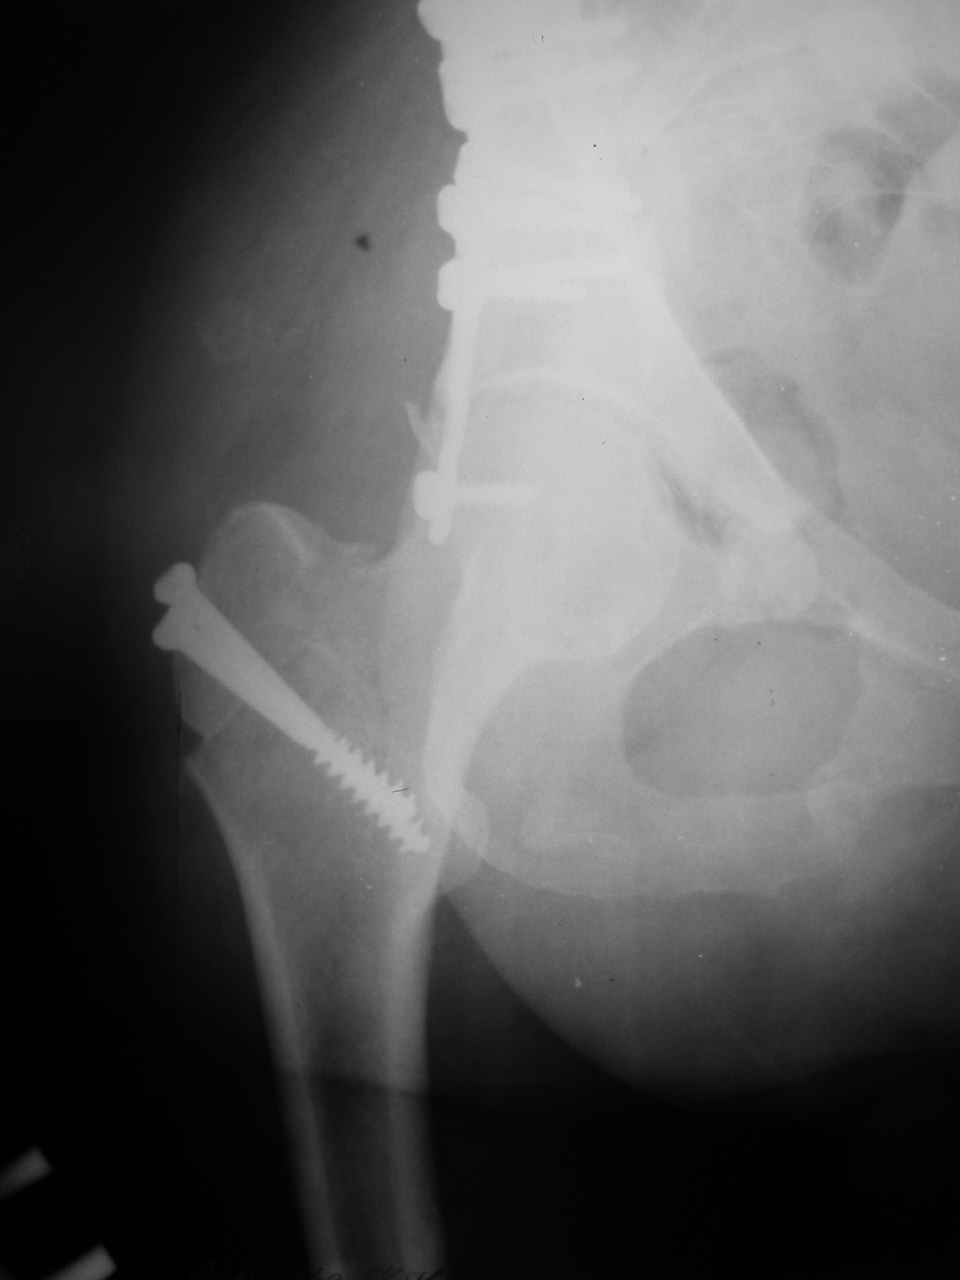

Сложностью, ассоциативностью характера перелома, я бы с радостью воспользовался мининвазивной перкутанной фиксацией винтами, но боюсь, что результат был бы ещё хуже, техникой непрямой репозиции перелома не владею, поэтому пытаясь получить анатомичную впадину приходится широко открывать, по крайней мере пока, а дальше буду пытаться уменьшать пространство...

> передним доступом на двухколонный перелом?

Илеофеморальный доступ не совсем передний и сравнительно с илеоингвинальным, и Кохера-Лангенбека открывает весь наружный таз кроме самых передних отделов лонных костей, фиксацию которых я не ставил в задачу. Обширность диссекции, большая длительность операции и более высокий риск гетерооссификации - отрицательные моменты в обмен на возможность легче ориентироваться.

Комбинированные доступы - хорошая альтернатива, меньший процент осложнений, но я заметил , что без сбора *мозаики* безымянной кости сложно отрепонировать переднюю колонну, а с нерепонированной передней колонной невозможно анатомично собрать заднюю колонну и соотв. фрагменты стенки - так.что все равно открывать придется широко. Поэтому выбирая комбинированный

подход, передний доступ должен был бы быть продлен до задней трети крыла безымянной кости, а задний - практически до того же уровня, оставляя 6-7 см мостик. При этом вместо одного послеоп. рубца у больного остаются два сравнительно длинных.

Вопрос доступа к вертлужной впадине при остеосинтезе задача не простая. Конечно, у Летурнеля и Тайла всё давно описано, нам остается только брать на вооружение. Но сами понимаете, что не бывает двух одинаковых ситуаций, поэтому в каждом случае вопрос решается сугубо индивидуально. Наша главная цель - восстановить анатомию с нанесением минимальной дополнительной травмы тазобедреннному суставу, думаю с этим никто не поспорит. Расширенный илиофеморальный доступ уж слишком травматичен (как сказал один коллега "таз лежит отдельно, больной отдельно").Стоит ли делать из пациента анатомический препарат для того чтобы легче ориентироваться. Да и нужно ли собирать всю "мозаику"? Мы применяли при таких операциях своеобразную операционную хитрость - сначала устраняли грубое смещение крыла под гребнем с фиксацией так называемой "плавающей" пластиной (временно фиксированной на двух винтах)- доступ или продлевали боковой, или делали небольшой дополнительный разрез над гребнем. Это позволяло устранить грубое смещение и захождение отломков тела повздошной кости, что значительно облегчало репозицию и остеосинтез впадины над сводом. Основное внимание конечно же уделяли нагружаемому задне-верхнему отделу. Сообщите ваш адрес, пришлю схемы и рентгенограммы.